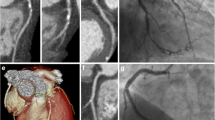

This study is a prespecified secondary analysis of the CAD-Man trial and is included in the published study protocol [8]. To be eligible for the study and randomization to coronary CT or ICA, patients needed to have suspected CAD and a clinical indication for ICA. In addition, patients had to have a maximum of two of the three criteria for typical angina pectoris (retrosternal chest discomfort, precipitation by exertion, and prompt relief within 30 s to 10 min by rest or nitroglycerine) [8]. The following exclusion criteria were used for the trial: two or more positive tests indicating ischemia, no sinus rhythm, signs of myocardial infarction (persistent ST segment elevation, creatine phosphokinase-MB > 24 U/L, or pulmonary edema due to ischemia), refusal or were incapability of providing informed consent, inability to hold the breath for 5 s, younger than 30 years, or history of or receiving dialysis [8]. The coronary CT procedure included both a non-contrast coronary artery calcium acquisition and a post-contrast CT angiography. No patients had prior coronary CT or ICA. After study enrollment and provision of informed consent, patients were randomly assigned to initial evaluation with either CT or ICA as previously described [8]. If CT was positive for CAD on non-invasive angiographic assessment, patients were then recommended to undergo ICA to confirm the diagnosis before initiation of treatment. Explanations about the imaging tests to the patients prior to their performance were provided by clinical staff. Images were shown during the ICA using on-site monitors by the interventional cardiologists in charge and after the CT procedure using workstations by the radiologists in charge using curved multiplanar reformations and three-dimensional renderings (Fig. 1).

Patient imaging examples. Example of negative coronary CT (A) and negative ICA (B). A Multiplanar reconstruction of the left main and left anterior descending of a patient randomized to coronary CT angiography without pathological findings, CAD was excluded. B Patient example of normal invasive coronary angiography showing strong vessels of the left coronary artery and its branches of the left anterior descending and left circumflex artery, CAD was excluded